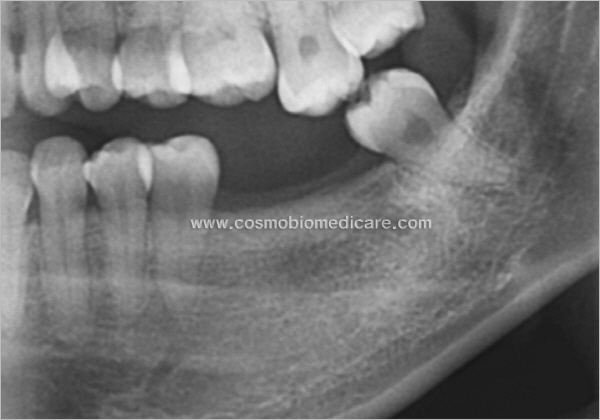

Clinical Cases

• Case1